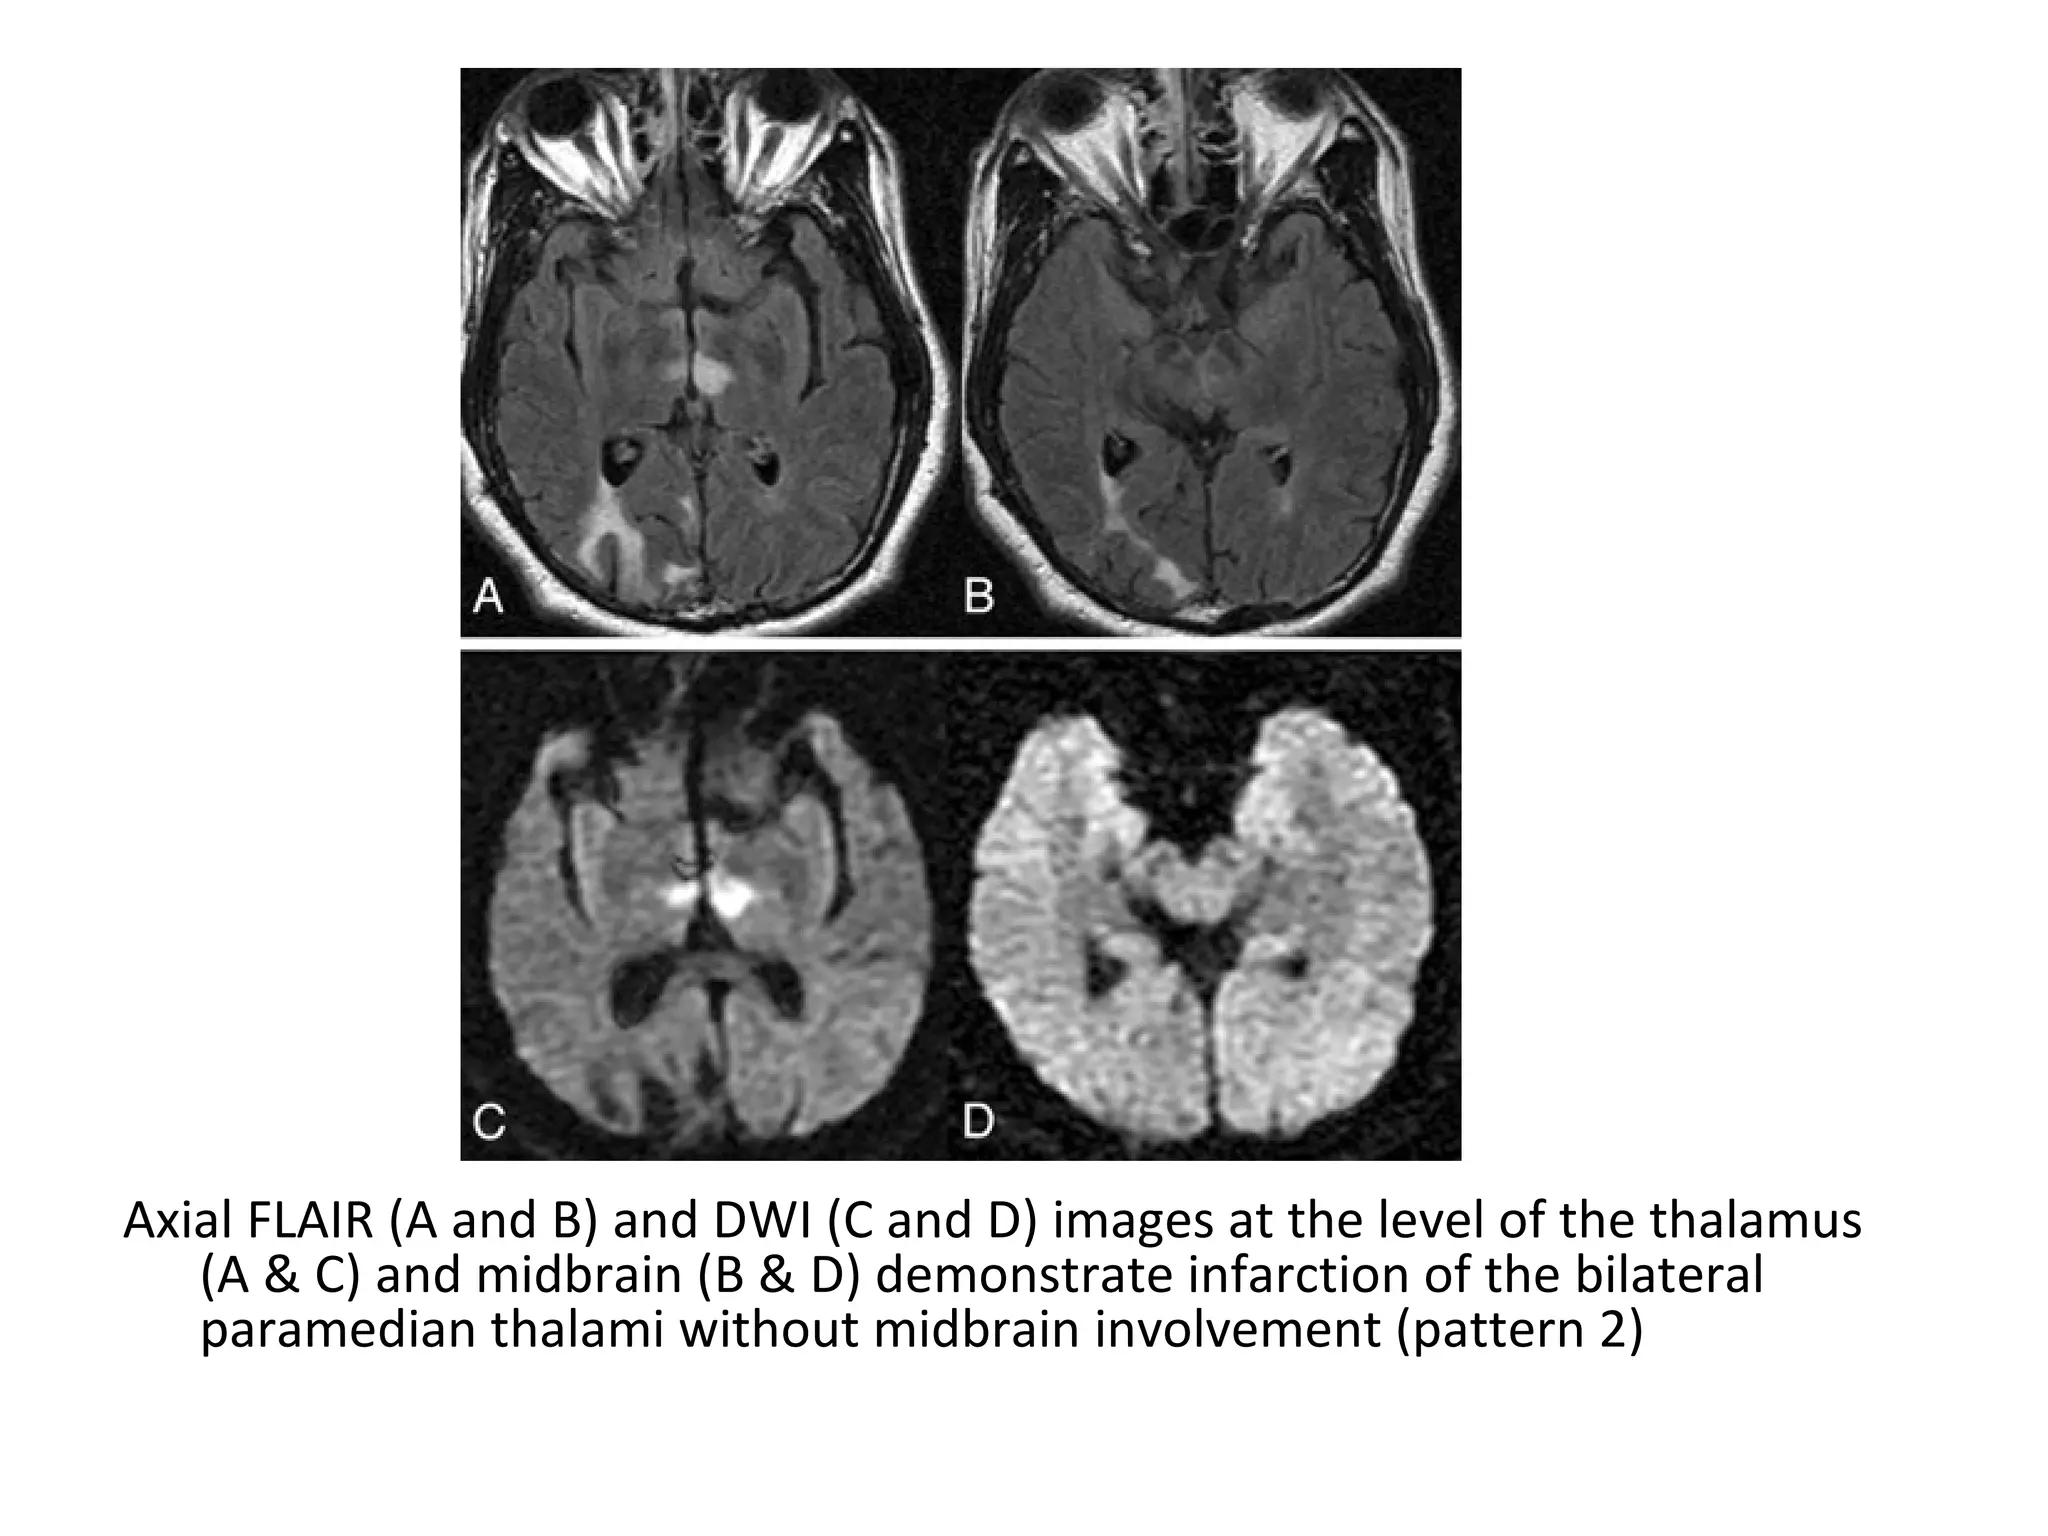

Axial FLAIR (A and B) and DWI (C and D) images at the level of the thalamus

(A & C) and midbrain (B & D) demonstrate infarction of the bilateral

paramedian thalami without midbrain involvement (pattern 2)